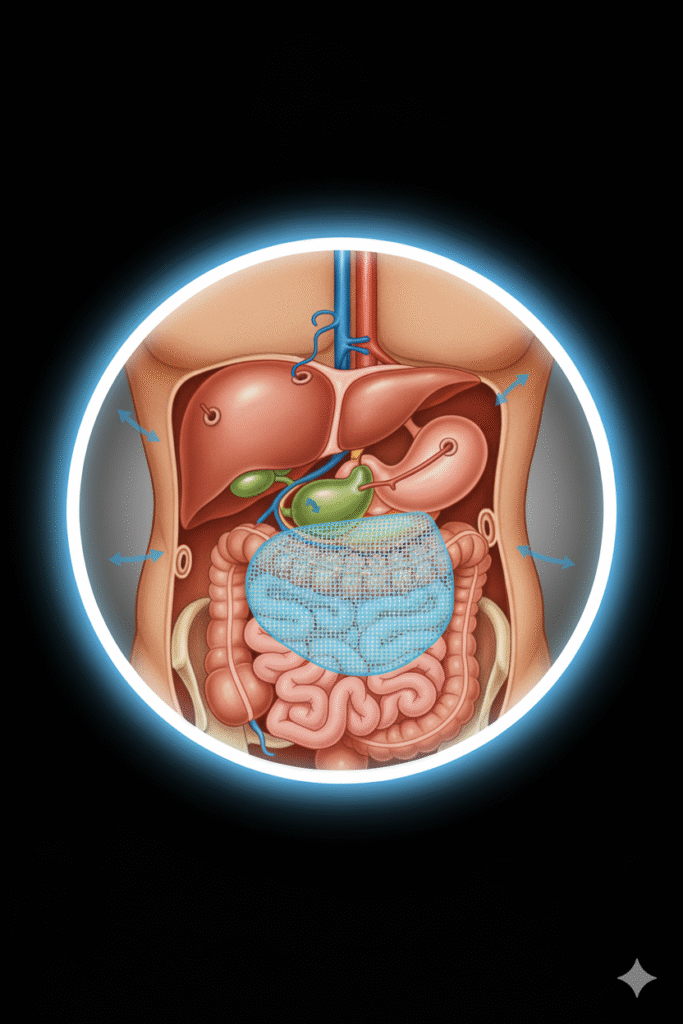

La cirugía de hernias en Monterrey ha evolucionado significativamente gracias a técnicas mínimamente invasivas y materiales de última generación que garantizan mejores resultados y una recuperación más rápida. Nuestro compromiso es devolverte tu calidad de vida con procedimientos seguros, efectivos y personalizados según tus necesidades.

¿Has notado un bulto o abultamiento en tu abdomen, ombligo o ingle? ¿Sientes dolor o molestias al realizar esfuerzos físicos, toser o levantar objetos? Las hernias son más comunes de lo que imaginas y requieren atención médica especializada para evitar complicaciones graves. En Monterrey, contamos con cirujanos expertos dedicados a brindarte la solución más efectiva y segura.

¿Qué es una Hernia y Por Qué Necesita Tratamiento?

Una hernia ocurre cuando un órgano interno o tejido sobresale a través de un punto débil en la pared muscular o tejido conectivo que normalmente lo contiene. Imagina una llanta con un punto débil en su superficie: la presión interna hace que ese punto se abulte hacia afuera. De manera similar, las hernias se manifiestan como protuberancias visibles o palpables.

Tipos de Hernias que Tratamos

La cirugía de hernias en Monterrey que realizamos abarca todos los tipos de hernias, cada una con características particulares: